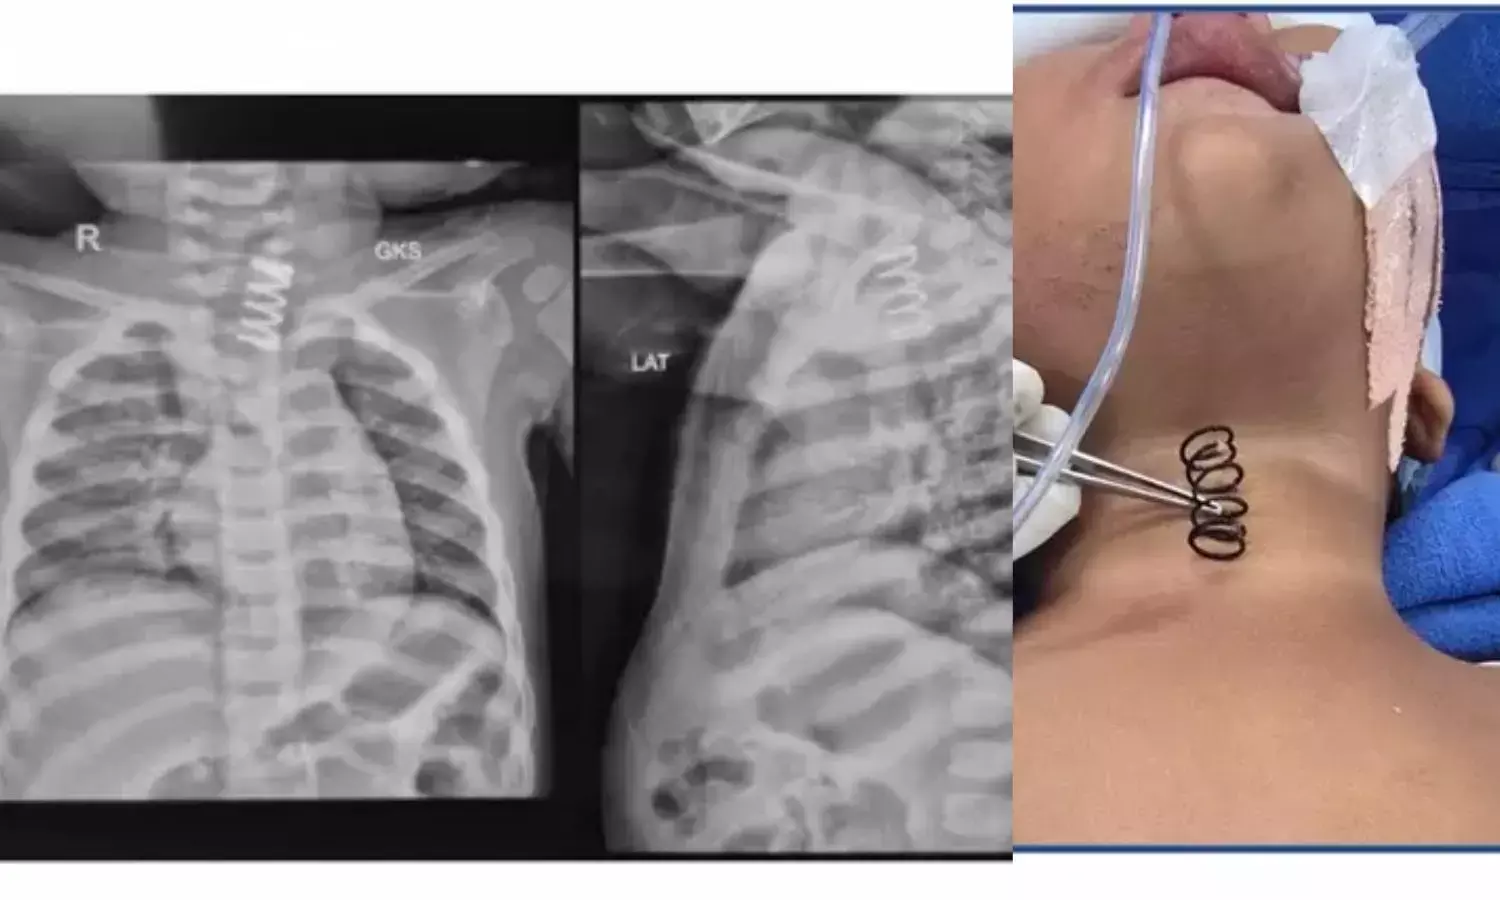

The child, who is from Yamunanagar, was brought to the hospital after suffering from continuous vomiting for nearly a week and refusing food for two days. Concerned about her worsening condition, doctors conducted a detailed examination. An X-ray revealed a large metal spring lodged in the upper part of her oesophagus, also known as the food pipe. Doctors also found ulcerations along the oesophageal lining, indicating that the object had caused significant internal injury.

According to AIIMS, the metal spring was unusually thick and much larger than common springs found in items like pens. It measured approximately half an inch in width and was around 1.5 to 2 inches long. Due to its size and shape, the spring had become firmly stuck in the child’s oesophagus, making removal extremely challenging.

At AIIMS, a specialised team led by Professor Dr. Vishesh Jain from the Department of Paediatric Surgery planned a carefully controlled endoscopic procedure. Using advanced endoscopic techniques in the operating room, the doctors slowly and precisely rotated the spring to disengage it from the oesophageal wall. Extreme caution was taken to avoid perforation or further injury to the food pipe.